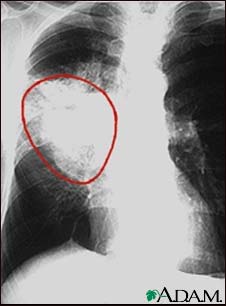

SCLC is the most aggressive form of lung cancer. It usually starts in the breathing tubes (bronchi) in the center of the chest. Although the cancer cells are small, they grow very quickly and create large tumors. These tumors often spread rapidly (metastasize) to other parts of the body, including the brain, liver, and bone.

- Chest x-ray

Usually, if a biopsy shows cancer, more imaging tests are done to find out the stage of the cancer. Stage means how big the tumor is and how far it has spread. SCLC is classified as either: